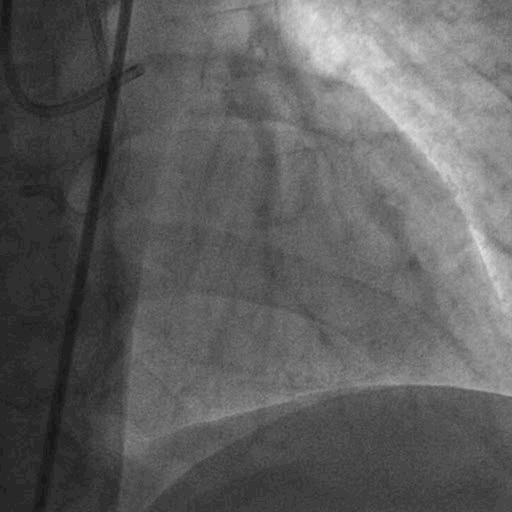

术前造影:

双侧造影:

CASE 2